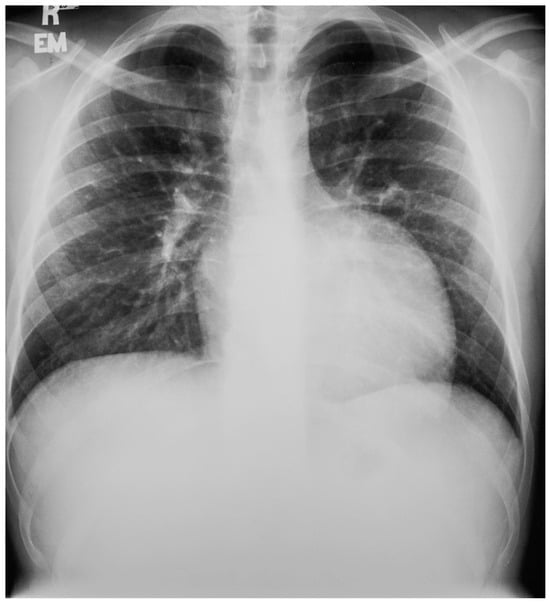

The heart is normally anchored in the center of the chest by the pericardium. Between the visceral and the parietal pericardia is 25–50 mL of pericardial fluid, which reduces friction during cardiac contraction. When the left portion of the parietal pericardium is completely absent, the heart shifts to the left hemithorax and the patient often presents with paroxysmal, stabbing chest pain that is nonexertional [2]. This pain has been attributed to episodic torsion of the great vessels because the heart is unmoored. Physical examination usually reveals cardiac apical displacement by palpation. Heart sounds, including splitting of S2, are normal. There is often a soft ejection systolic murmur that is best heard at the left sternal border. Although CCALPPP might be an uncomfortable congenital heart disease, all 10 patients studied by Gatzoulis et al. [2] were alive and well more than 10 years after diagnosis. In cases where the left pericardial defect is partial, especially when there is a foramen-type partial absence of the left pericardium, the left atrium can herniate into the defect and strangulate the heart. When recognized, this partial defect must be remedied. The incidence of congenital absence of the pericardium, both complete and partial, is very rare. As many cases are asymptomatic, the majority of cases are recognized unwittingly at autopsy or during thoracotomy, when addressing a different problem [2]. The PA CXR in CCALPPP demonstrates levoposition of the heart, loss of the right heart border as it overlies the vertebral bodies, and prominence of the pulmonary artery segment (Figure 1).

Figure 1.

Posteroanterior chest X-ray in congenital complete absence of the left portion of the parietal pericardium: A 30-year-old female was referred to a cardiologist because of an unusual chest X-ray done as part of an executive physical. She was asymptomatic and her vital signs and heart sounds were normal and there was no heart murmur or arrhythmia. The image is well centered, there is a good inspiration and the C-T ratio is <0.5. The heart is shifted into the left chest and the right heart border is obscured because it overlies the dorsal vertebral bodies. The pulmonary artery segment (outlined with blue dots) is enlarged but the pulmonary vascularity is normal, making left to right shunting unlikely. Echocardiography and Cardiac MRI confirmed she had CCALPPP. She was reassured. No treatment was necessary.